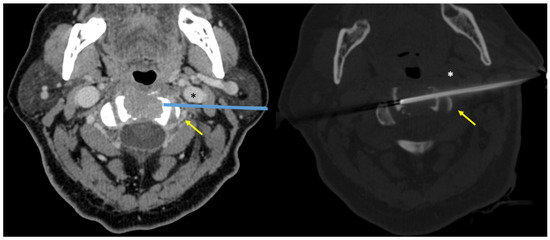

| Patient n° | Age, Sex | Lesion Location | Radiologic Feature | Needle Gauge | Intravenous Contrast Media Injection | Biopsy Approach | Histological Diagnosis on Biopsy Specimen |

|---|---|---|---|---|---|---|---|

| 1 | 18, M | C2 | Osteolytic | 14 | No | Posterior | Aneurismal bone cyst |

| 2 | 71, M | C2 | Osteolytic | 14 | No | Posterior | Multiple myeloma |

| 3 | 49, M | C1 | Osteolytic | 14 | No | Posterior | Aggressive hemangioma |

| 4 | 64, F | C2 | Osteolytic | 14 | Yes | Lateral | Multiple myeloma |

| 5 | 64, F | C1 | Osteolytic | 14 | No | Posterior | Metastasis (breast cancer) |

| 6 | 40, F | C2 | Osteolytic | 14 | No | Posterior | Metastasis (breast cancer) |

| 7 | 39, M | C1 | Osteolytic | 14 | No | Posterior | Multiple myeloma |

| 8 | 16, M | C2 | Osteolytic | 14 | No | Posterior | Aneurismal bone cyst |

| 9 | 79, M | C2 | Osteolytic | 14 | Yes | Lateral | Non-diagnostic |

| 10 | 23, M | C1 | Osteolytic | 14 | No | Posterior | Blood and fibrin (non-diagnostic) |

| 11 | 73, M | C1 | Mixed | 14 | No | Posterior | Metastasis (prostate cancer) |

| 12 | 52, F | C0 and C1 | Osteolytic | 14 | Yes | Posterior | Multiple myeloma |

| 13 | 28, F | C1 | Osteolytic | 14 | No | Posterior | Aneurismal bone cyst |

| 14 | 72, F | C1 and C2 | Sclerotic | 12 | No | Posterior | Pseudogout |

| 15 | 51, F | C1 and C2 | Osteolytic | 14 | Yes | Posterior | Rare giant cells (non-diagnostic) |

| 16 | 86, F | C0 | Osteolytic | 12 | No | Posterior | Metastasis (breast cancer) |